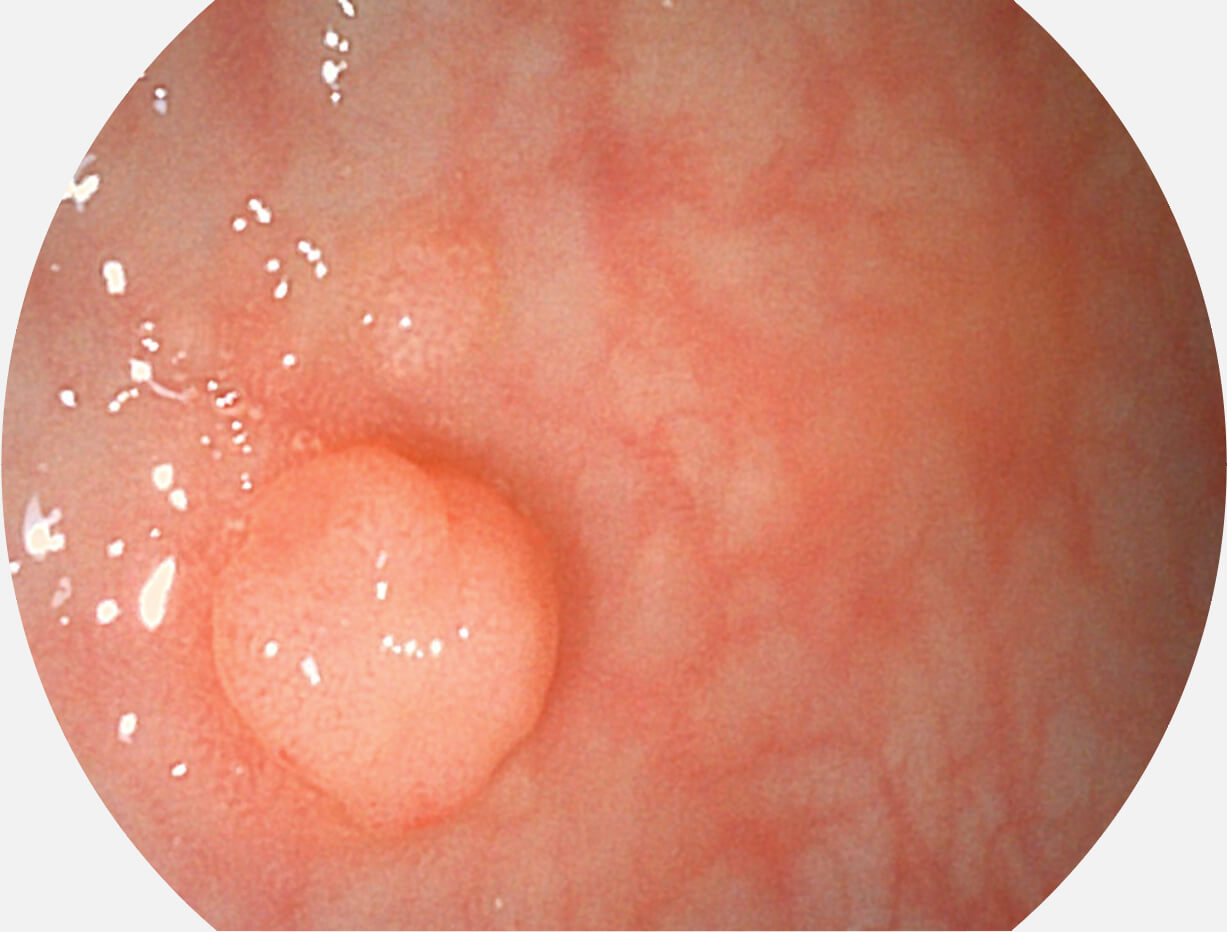

白光图像